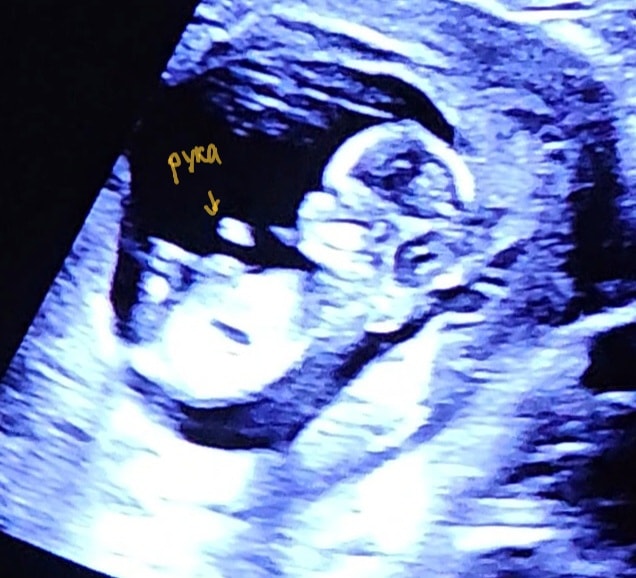

Сегодня прошла 1 скрининг. Кровь и риски придут попозже, а вот результат узи дали сразу. Срок устно назвали 12+4, записали 12+3. Чуть меньше, чем по месячным, как-то так и было овуляция. Ктр 60 мм, остальное в фото.

Врач сказал: "сидит как в гамаке, скрестив ноги") Шевелиться мадам совсем не хотела, как её только не тормошили датчиком. Смотрели через живот, что меня удивило. Думала, будет ещё вагинально. Поэтому прям супер кадров нет. Для них на сроке попозже думаю платно сходить на узи.